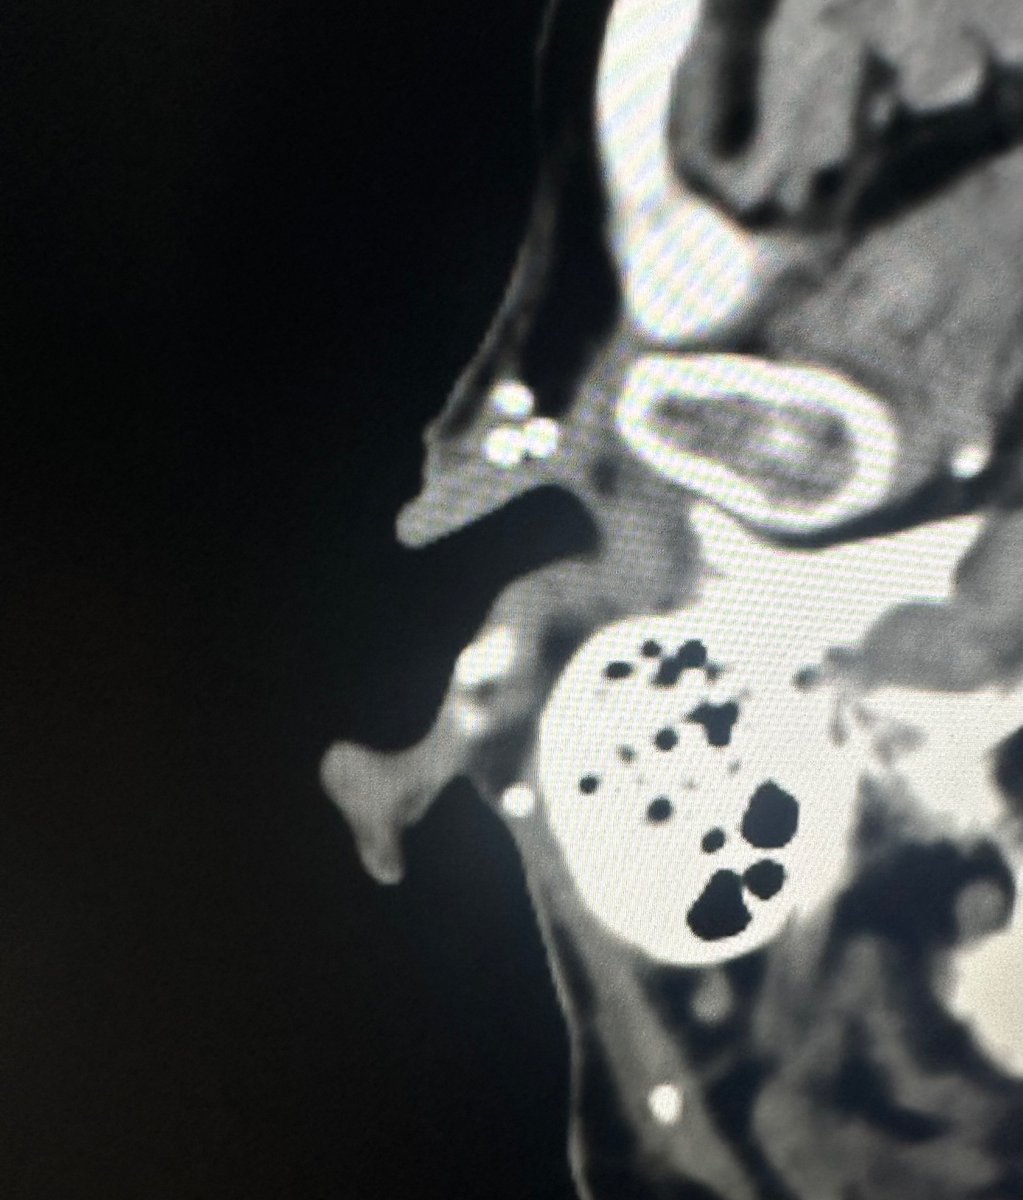

Sometimes the weirdest tidbits pique my interest in neurorads. For example, seeing this patient’s ears and knowing he’s likely experienced a few fistfights. Also realizing he was likely fighting a right handed individual (left ear shows more chronic damage)- “cauliflower ear”

Miriam Peckham tweet mediaMiriam Peckham tweet media